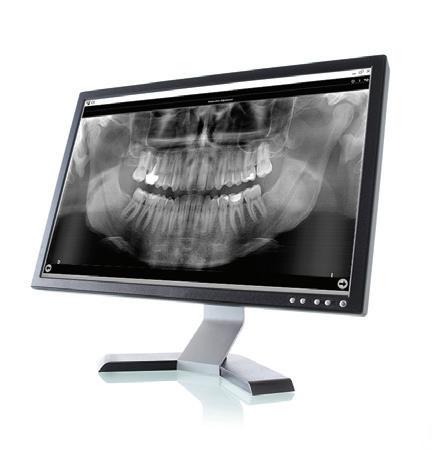

TrollBag for røntgensensorer

Supermyke trekk for sensorer og fosforplater. Helt uten lateks, lukt, smak og skarpe kanter. Lett å ta på og av, uten å ødelegge sensoren.

Tips: XL-trekket dekker både sensor og røntgenholder. En superenkel løsning som gjør hygienearbeidet mye enklere.

TrollBag for fosforplater

Supermyke poser for fosforplater.

Helt uten lateks, lukt, smak og skarpe kanter. Lett å ta på og av.

Leveres på rull i praktisk dispensereske.

Dekker sensor.

3,6*22cm.

500-pk. Før 1.048,#1

734,-

Vnr. 6509

#13190089

Dekker sensor. 4,0*22cm. 500-pk. Før 1.048,#13190090

Vnr. 6500

Fosforplate #1 49x29mm. 500-pk. Før 1.298,-

Fosforplate #2 50x36mm. 500-pk. Før 1.298,-

Vnr. 7783 974,-

Vnr. 7784

#13190401 #13190402